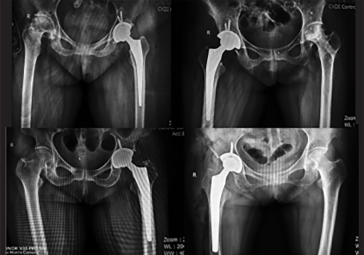

· 精準(zhǔn)執(zhí)行手術(shù)方案,消除徒手操作誤差。

· 精準(zhǔn)高效執(zhí)行手術(shù)操作,實(shí)時(shí)安裝角度顯示,誤差控制在1°以內(nèi)。